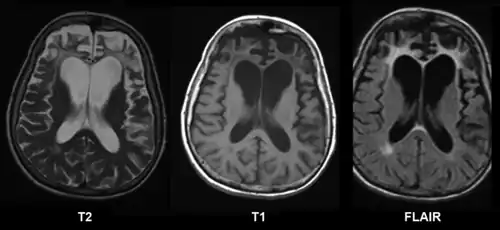

A range of neuropsychological tests are available for clarifying the nature and extent of frontal lobe dysfunction. For example, concept formation and ability to shift mental sets can be measured with the Wisconsin Card Sorting Test, planning can be assessed with the Mazes subtest of the WISC.[3] Frontotemporal dementia shows up as atrophy of the frontal cortex on MRI.[20] Frontal impairment due to head injuries, tumours or cerebrovascular disease will also appear on brain imaging.[4]